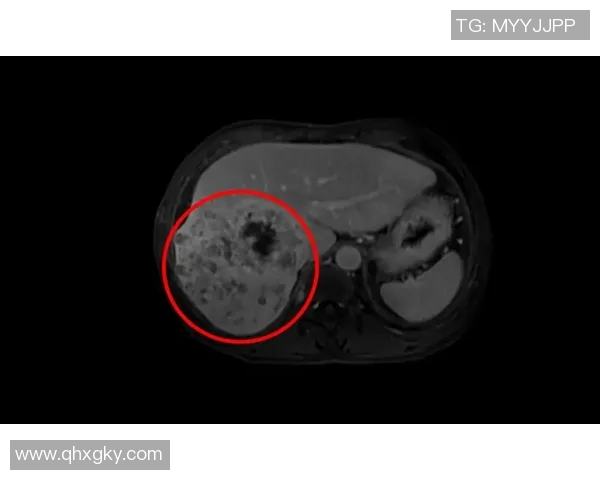

某位著名足球明星因肝癌而英年早逝,这一消息震惊了整个体育界和他的粉丝们。他在场上的表现可谓光芒四射,无论是进球还是助攻,都让人铭记于心。然而,在他光鲜亮丽的外表下,却隐藏着不可告人的健康隐患。随着时间推移,他逐渐感到身体的不适,但由于工作繁忙,他并没有及时就医,直到症状加重才不得不面对现实。

在最终被诊断为晚期肝癌时,这位球星已然错过了最佳治疗时机。他接受了一系列治疗,但病情依旧恶化。在抗击疾病的过程中,他面临的不仅是身体上的痛苦,还有精神上的煎熬。作为公众人物,他不仅要承受个人健康问题,还要面对外界压力和舆论。这些都让原本充满活力的人生蒙上了一层阴影。